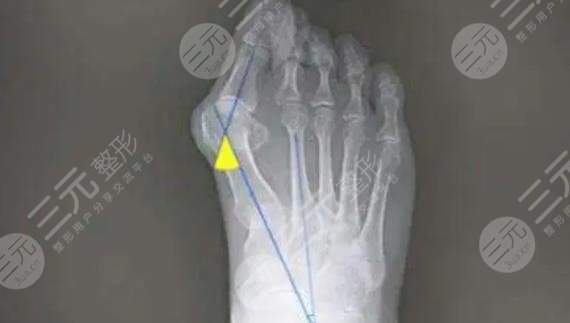

苏敬达医生所开展的大脚骨手术,是以微创的手术方式所开展,术中借助于可移动的骨骼透视系统进行实时成像操作,所以准确度相对较高,可以有效的减少手术中的损伤,为爱美者美化足型的同时,穿鞋走路更加轻松!无需住院,随治随走,让每位爱美人士都能满足和体验人性化的美足服务!实际手术中也是能够依据顾客实际的足部情况,美学标准进行手术方案的设计,可实施性强,术后足部线条更为流畅和纤细!

微创祛大脚骨:

目前临床上针对于大脚骨的手术方式是比较多的,微创大脚骨的手术方式主要是以微创的方式进行剥离,手术创口只有针眼大小,手术操作期间也是有专业的成像设备提供直视化的操作,整个剥离过程对于神经、组织损伤较小,另外在分离脚骨的同时,还能更好的帮助矫正受术者的脚型,术后只要做好加压包扎,一般都是可以收获比较满意的足型效果,所以目前微创祛大脚骨手术方式是很受欢迎的!临床反馈效果也比较好!该类手术是处于骨科手术,也可以划分为外科手术,手术操作多是在局麻下进行,操作时长因大脚骨的难以程度而定!建议爱美者选择正规的医院开展手此类手术!